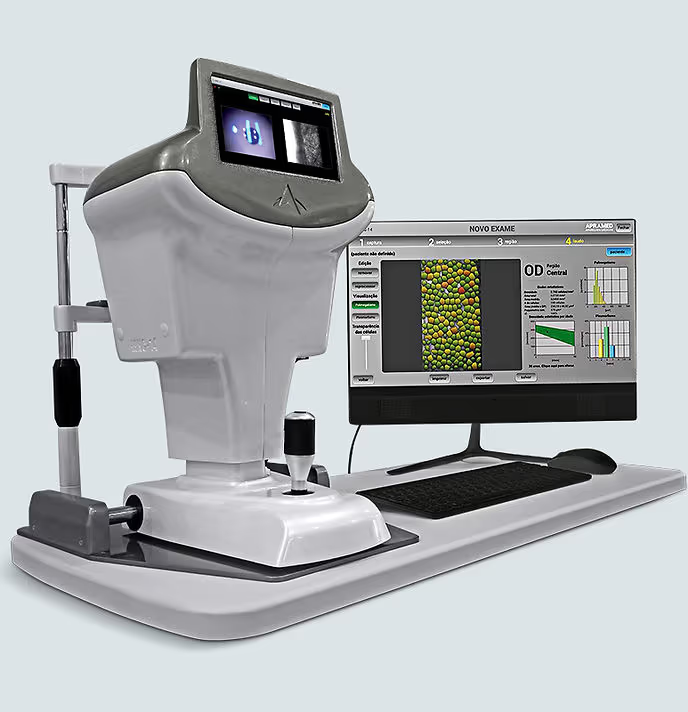

- Biometria óptica: mede a curvatura da córnea e o comprimento do olho com luz, calculando o grau exato da lente intraocular.

- Microscopia especular de córnea: avalia a saúde do endotélio corneano, a camada interna da córnea.

- Topografia de córnea: essencial em pacientes que vão receber lente multifocal ou tórica, pra confirmar se a lente é indicada.